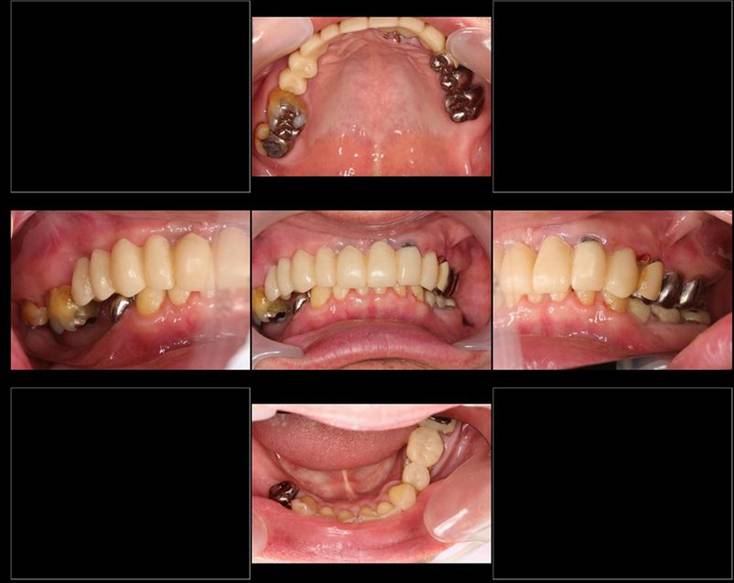

歯周病で抜歯せざるを得ず、インプラントを希望されたケース(使用インプラントはスプライン)

術前。すべての歯が歯周病の末期状態でブリッジ全体がうごいて噛めないとの訴え。右上の犬歯が腫れていました

固定式のブリッジが入っていましたが歯周病で動いています

下顎前歯部には歯石の沈着がみられます

術後。上部構造はハイブリッドレジンです。しっかり嚙めるようになり喜んでいただきました。

上部構造装着後6年。ハイブリッドレジンを使用したため、少し艶がなくなってきました。上部構造の材料には金属、ハイブリッドレジン、セラミックなどがあります。セラミックはきれいですが欠けやすいため、最近はフルジルコニアを使っています。

上顎 少しすり減ってきました。

下顎。12か月に一度メインテナンスをしています。

インプラント装着後6年。順調に経過しています。12か月毎のメインテナンスをしています。